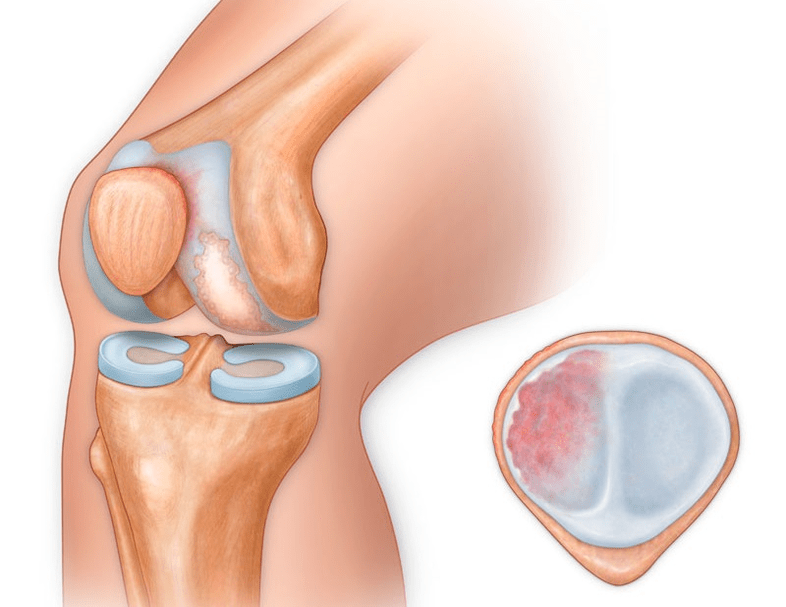

In addition to the inside or outside part of the knee, osteoarthritis can also affect the surfaces between the kneecap and the intercondylar groove of the femur.This option is calledpatellofemoral arthrosis.

Its cause is usually a subluxation, fracture or lateralization of the patella.

In the second phase, the cartilaginous layer becomes significantly thinner and in some places is completely absent.Osteophytes appear along the edges of the joint surfaces.The qualitative and quantitative characteristics of the synovial fluid of the joint change: it becomes denser, more viscous, which leads to a deterioration of its nutritional and lubricating properties.The pain is more prolonged and intense and a crunching sound is often heard during movement.There is mild to moderate limitation of movement and slight deformation of the joint.Taking analgesics helps relieve pain.

Lack of cartilage in most affected areas, severe sclerosis (hardening) of the bone, many osteophytes, and a strong narrowing or absence of the joint space.The pain is almost constant, the gait is impaired.Mobility is severely limited and joint deformation is evident.NSAIDs, physiotherapy and other standard methods for treating knee osteoarthritis are ineffective.